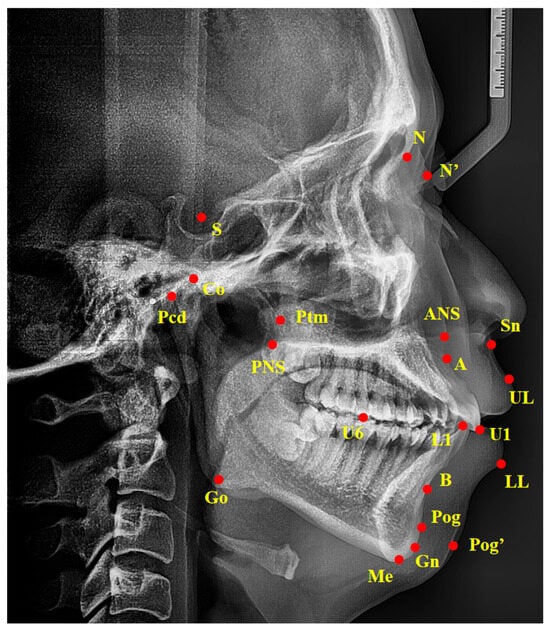

| Measurements | Description |

|---|---|

| Angular measurements (°) | |

| SNA | Angle between point S and A at N |

| SNB | Angle between point S and B at N |

| ANB | Angle between point A and B at N |

| PP-FH | Angle between PP plane and FH plane |

| PP-GoGn | Angle between PP plane and line Go–Gn |

| OP-SN | Angle between occlusal plane and SN plane |

| MP-SN | Angle between mandibular plane and SN plane |

| FH-MP | Angle between FH plane and mandibular plane |

| SGn-FH | Angle between line S–Gn and FH plane |

| NBa-PtGn | Angle between line N–Ba and line Pt–Gn |

| U1-L1 | Angle between the long axis of upper incisors and lower incisors |

| U1-SN | Angle between the long axis of upper incisors and SN plane |

| U1-NA | Angle between the long axis of upper incisors and line N–A |

| L1-NB | Angle between the long axis of lower incisors and line N–B |

| L1-FH | Angle between the long axis of lower incisors and FH plane |

| Z-Angle | Angle between line Z-line and FH plane |

| FH-N’Pog’ | Angle between FH plane and line N’Pog’ |

| N’-Sn-Pog’ | Angle between point N’ and Pog’ at Sn |

| Linear measurements (mm) | |

| Ptm-A | Distance between Ptm and A |

| Ptm-S | Distance between Ptm and S |

| Go-Pog | Distance between Go and Pog |

| Go-Co | Distance between Go and Co |

| Pcd-S | Distance between Pcd and S |

| N-ANS | Distance between N and ANS |

| ANS-Me | Distance between ANS and Me |

| S-Go | Distance between S and Go |

| U1-NA | Distance between U1 and line N–A |

| L1-NB | Distance between L1 and line N–B |

| U1-APo | Distance between U1 and line A–Pog |

| L1-APo | Distance between L1 and line A–Pog |

| U6-Ptm | Distance between U6 and Ptm |

| U1-PP | Distance between U1 and PP plane |

| U6-PP | Distance between U6 and PP plane |

| L1-MP | Distance between L1 and mandibular plane |

| L6-MP | Distance between L6 and mandibular plane |

| UL-EP | Distance between UL and EP plane |

| LL-EP | Distance between LL and EP plane |